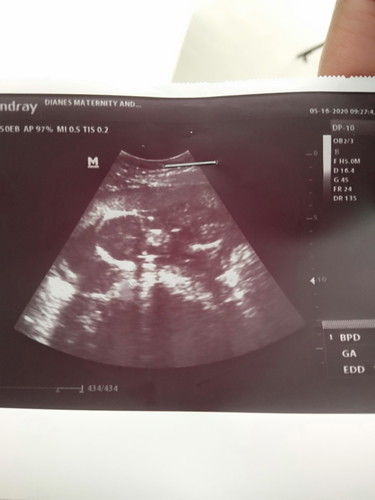

#1stimemom #firstbaby #1stpregnnt #theasianparentph nakakatuwa lng po yung lip ko kasi sobrang alaga niya saakin ako na yata yung pinaka maswerteng babae kasi, napakasipag ng lip ko pag nasa work siya focus siya sa ginagawa niya , then pag nasa bahay naman namin siya kahit may ginagawa siya pag need ko siya priority parin niya ako.. kasi kahit nasa bahay siya nag wowork parin siya with computer may mga tinatapos siya pero pag once na kailangan ko ng ganito inaalalayan niya parin ako lalo na pag tatayo ako or iihi , then lagi niya din akong pinag titimpla ng milk bago matulog or pag nararamdaman ko yung acid reflux ko sa madaling araw or pag nagugutom nmn ako siya yung nag aasikaso saakin sa pag kain , at maya maya niya ako tinatanong nang "honey if yiu hungry pls tell me "sagot ko nmn kahit na busog pa ako ok honey i will thanks then lagi niya ako kinikiss sa noo pag matutulog or pag kayakap ko siya basta mag kasama kmi ang sarap sa,pakiramdam na laging pinaparamdam sayo na mahal ka niya at importante ka sa knya at kahit anong gusto kong ipabili sa knya lagi siyang andiyan may dala dala hehe ayaw niya rin akong mapagod or magkikilos kasama ko nmn palagi ang mga kapatid kong mga nakababata at mama ko kahit inaasikaso ako ng mama ko lalo na sa pagkain ko at alaga nmn ako ng mga kapatid ko at mama ko sobrang blessed din ako kasi inaalagaan parin ako ng lip ko hindi niya rin kmi pinababayaan ng baby ko sabi niya palagi saakin "honey , dont think about money or anything"wag din daw ako mag pa kastress sa ano mang bagay basta pag may problema ako sabihin ko sa knya kaya pag nakikita niya akong nakabusangot ang mukha ko ayun inaalam niya lagi kahit ayaw ko sabihin kasi ayaw kong mag alala siya saakin gusto niya talagang alamin kung na yung pinoproblema ko kaya ayun pag ilang araw pa lang siyang wala dito sa bahay namimis ko na siya agad at umiiyak ako namimis ko siya agad.. hehe mahal na mahal ko lip ko nag aaway kmi pero nag kakaayos nmn kami normal lng nmn saxmag partner yun .. napaka swerte ko kasi napakabait at responsableng partner at ama ... thanks Kay God ... share lng mga momsh...